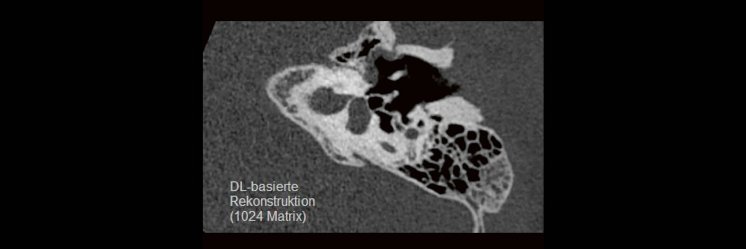

Die CT ist ein essentielles Routine-Verfahren in der Neuroradiologie. Bei steigender Bildqualität konnte die Röntgendosis mit neuen Technologien in der letzten Dekade deutlich gesenkt werden, was für die zielgerichtete und möglichst schonende Behandlung von Patienten von großer Bedeutung ist. Mit der Deep-Learning-Rekonstruktion steht ein neues Verfahren zur Verfügung, welches die Befunderhebung noch einmal deutlich verbessert. Technische Hintergründe und klinische Anwendungen im Rahmen der Neuroradiologie werden vorgestellt und diskutiert.

Im Vergleich zur Spiral-Computertomographie (SpCT) kann die Volumen-Computertomographie (VCT) hierbei Vorteile bieten. Mit der Verbesserung der auf künstlicher Intelligenz basierenden Rekonstruktionsalgorithmen kann nicht nur die Strahlendosis erheblich reduziert, sondern auch die diagnostische Aussagekraft erheblich verbessert werden. Technische Fortschritte mit Schwerpunkt auf KI-Algorithmen und deren umfangreiche klinische Anwendung werden vorgestellt und diskutiert.